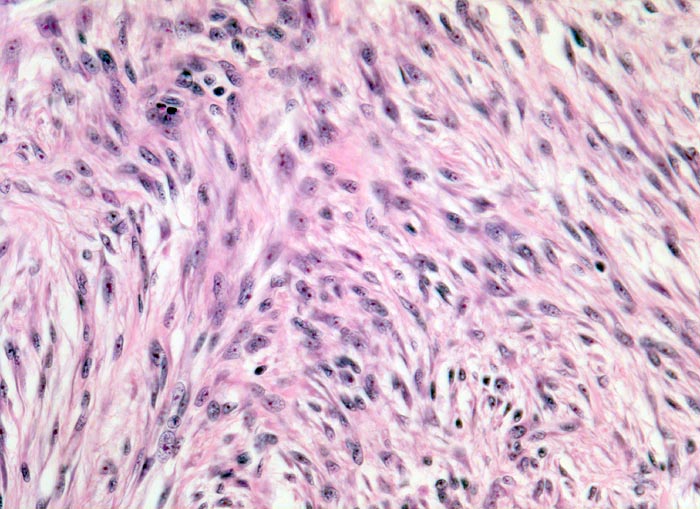

Zellreiches fibröses Histiozytom

benigner Tumor

Haut, Hand palmar, Finger

Spindelige Tumorzellen bilden ein geflechtartiges Muster. Die Morphologie erinnert an einen leiomyomatösen Tumor.

Ploidie: Diploid, DNS-Index 1,9. S-Phasen-Fraktion: 19,4%, hoch. Das Messergebnis spricht für eine hohe proliferative Aktivität entsprechend einem zellreichen fibrösen Histiozytom.

Tumorrezidiv interdigital.